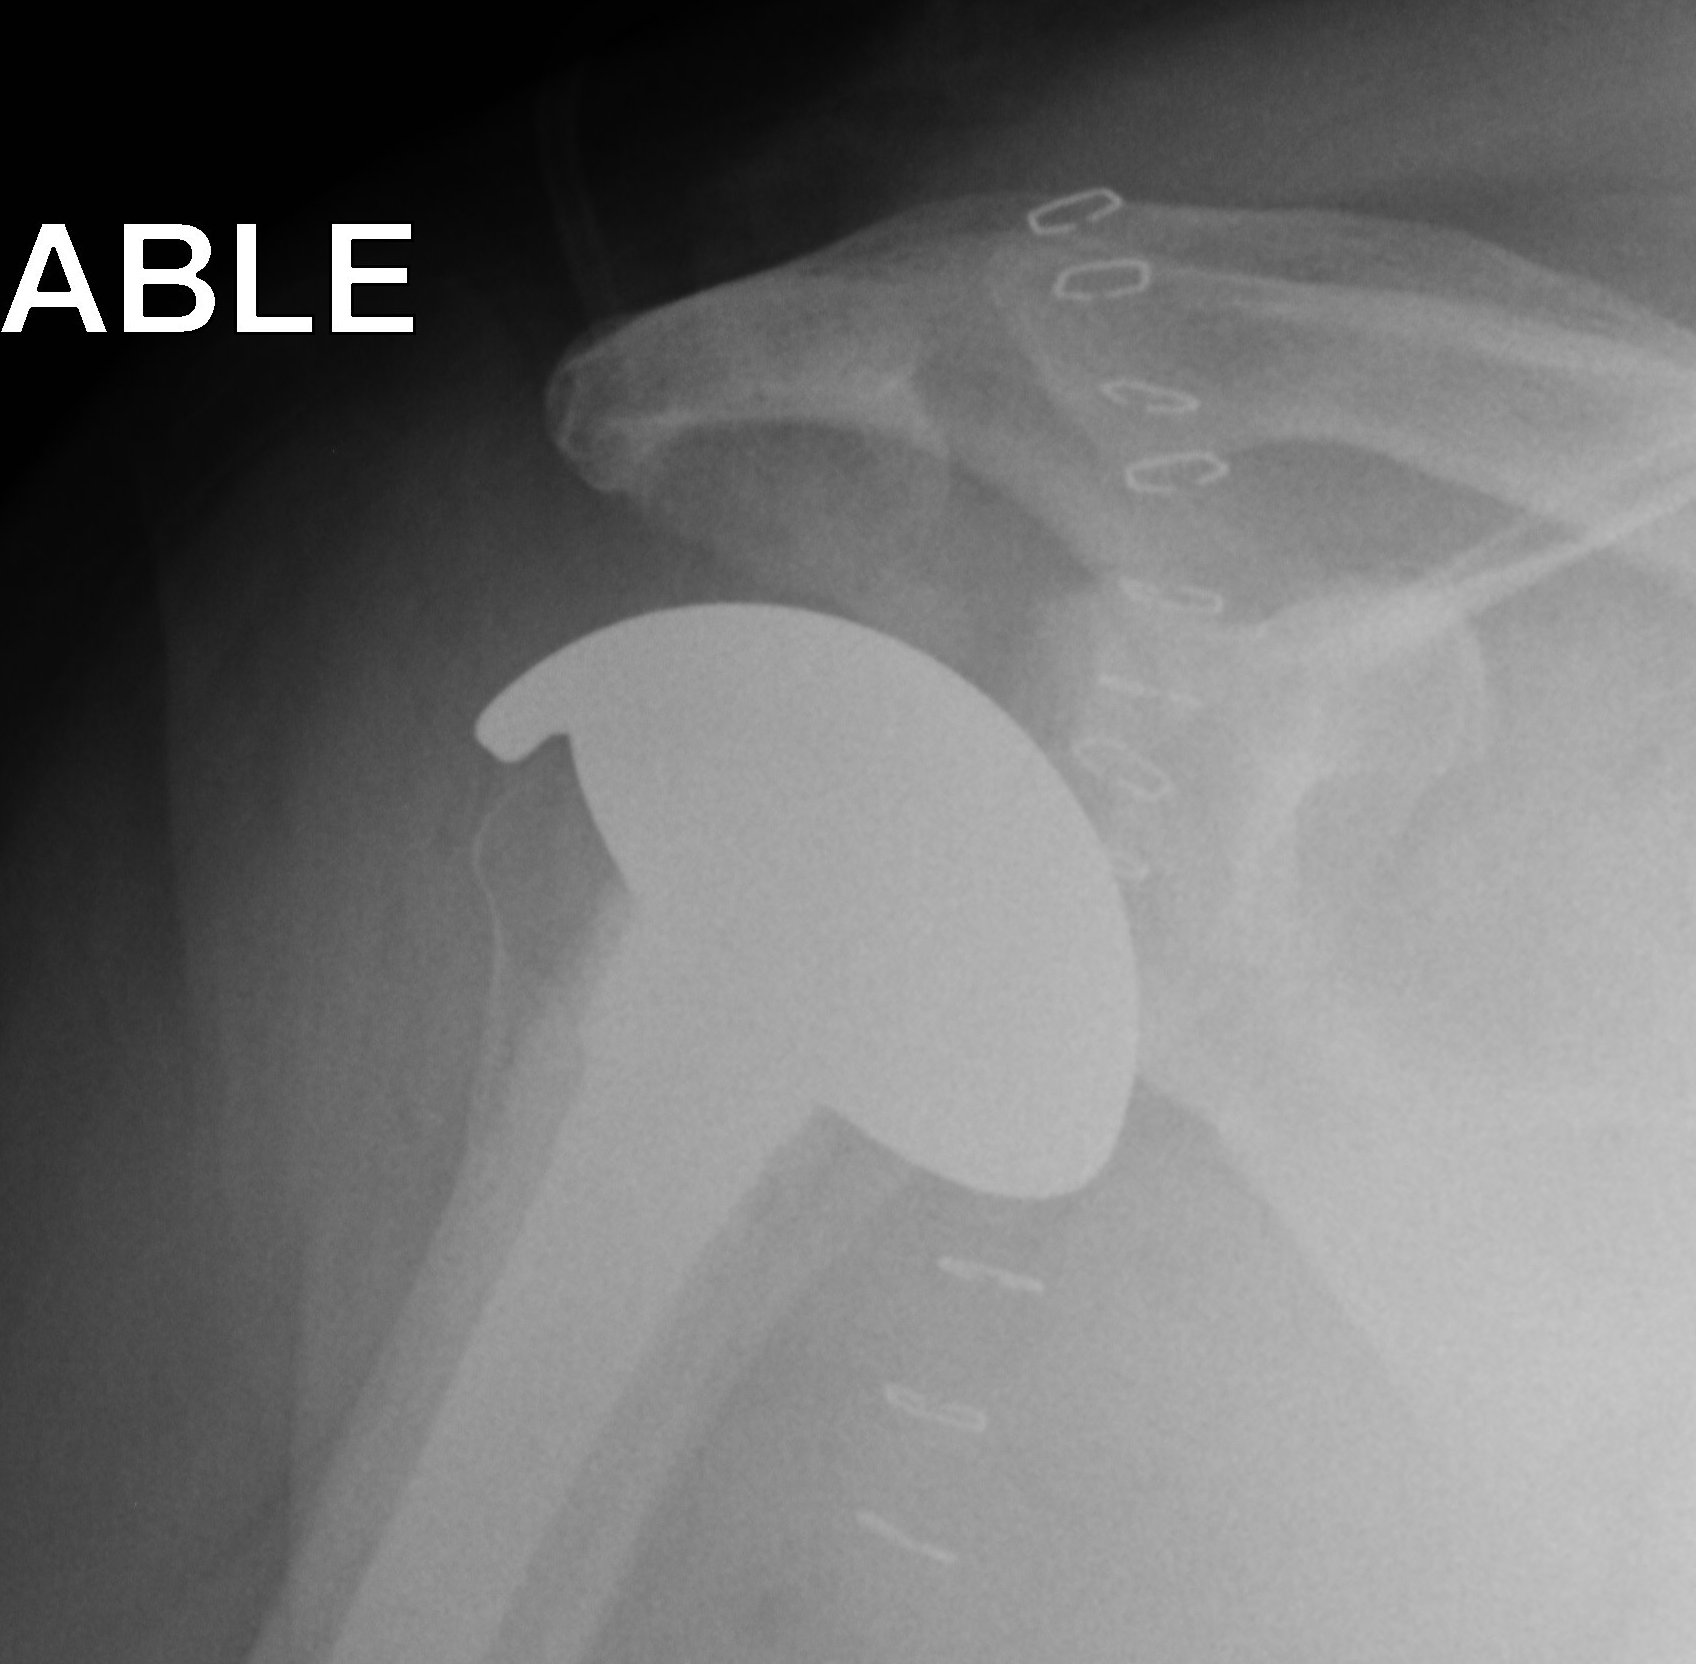

CTA Humeral Head / Extended Humeral Head Arthroplasty

Cuff Tear Arthropathy (CTA)

Extended humeral head prosthesis

- arc of surface > 180o

- allows articulation of lateral head with acromion

- increased articulation in abduction and external rotation